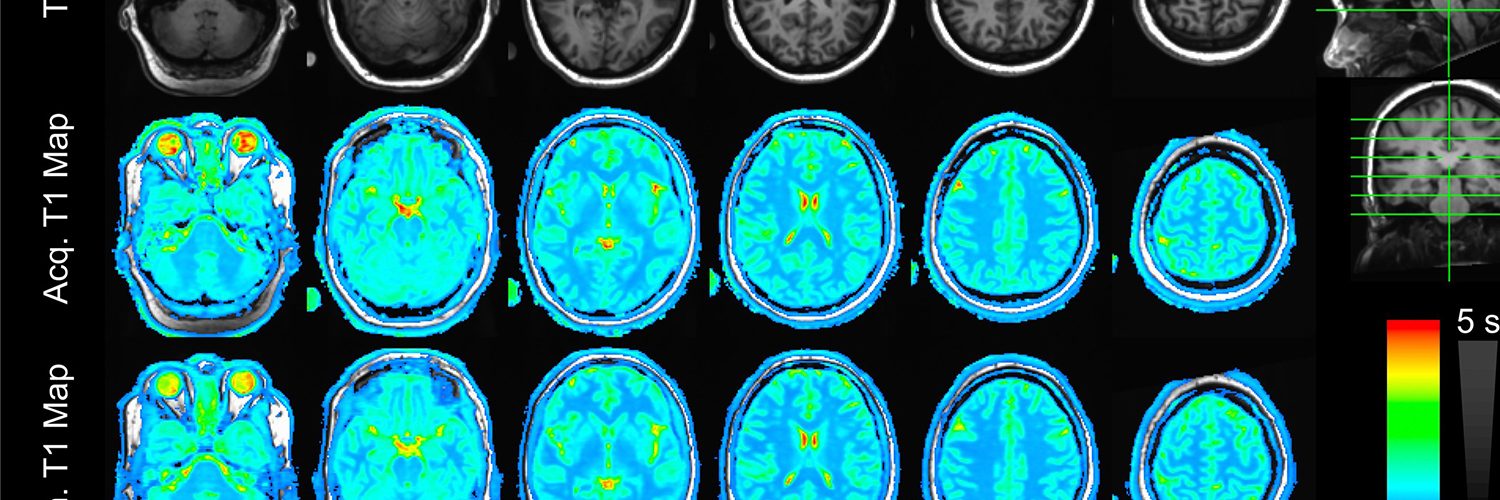

The Molecular Imaging Technology Research Program (MITRP) within the Department of Radiology is located in the Wisconsin Institutes for Medical Research (WIMR) Building at the University of Wisconsin, Madison School of Medicine and Public Health. Our group seeks to advance MRI, PET/MR, and PET/CT imaging techniques and technology to gain new structural and functional information to better detect and assess human disease.